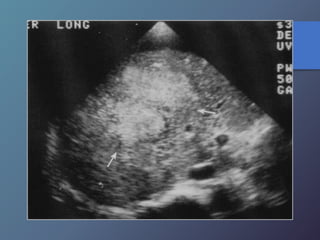

Cirrosis Hepática

Proceso difuso hepático caracterizado

por fibrosis y la conversión de la

arquitectura normal del hígado en

nódulos estructuralmente anormales.

• Redistribución de volumen. Índice

caudado/lob. Der. 0.65.

• Ecoestructura grosera.

• Superficie nodular.

• Nódulos de regeneración.

• Nódulos displásicos.

• Hipertensión portal: Ascitis, esple-

nomegalia, varices.

Características Ecográficas